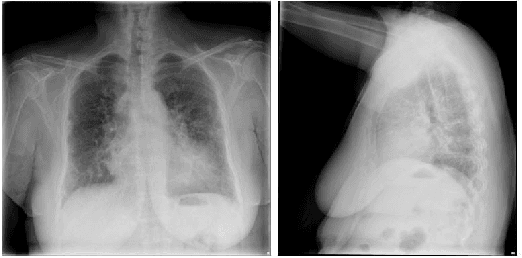

Abstract:The identification and localization of diseases in medical images using deep learning models have recently attracted significant interest. Existing methods only consider training the networks with each image independently and most leverage an activation map for disease localization. In this paper, we propose an alternative approach that learns discriminative features among triplets of images and cyclically trains on region features to verify whether attentive regions contain information indicative of a disease. Concretely, we adapt a distance learning framework for multi-label disease classification to differentiate subtle disease features. Additionally, we feed back the features of the predicted class-specific regions to a separate classifier during training to better verify the localized diseases. Our model can achieve state-of-the-art classification performance on the challenging ChestX-ray14 dataset, and our ablation studies indicate that both distance learning and region verification contribute to overall classification performance. Moreover, the distance learning and region verification modules can capture essential information for better localization than baseline models without these modules.

Abstract:Automatic medical report generation from chest X-ray images is one possibility for assisting doctors to reduce their workload. However, the different patterns and data distribution of normal and abnormal cases can bias machine learning models. Previous attempts did not focus on isolating the generation of the abnormal and normal sentences in order to increase the variability of generated paragraphs. To address this, we propose to separate abnormal and normal sentence generation by using two different word LSTMs in a hierarchical LSTM model. We conduct an analysis on the distinctiveness of generated sentences compared to the BLEU score, which increases when less distinct reports are generated. We hope our findings will help to encourage the development of new metrics to better verify methods of automatic medical report generation.